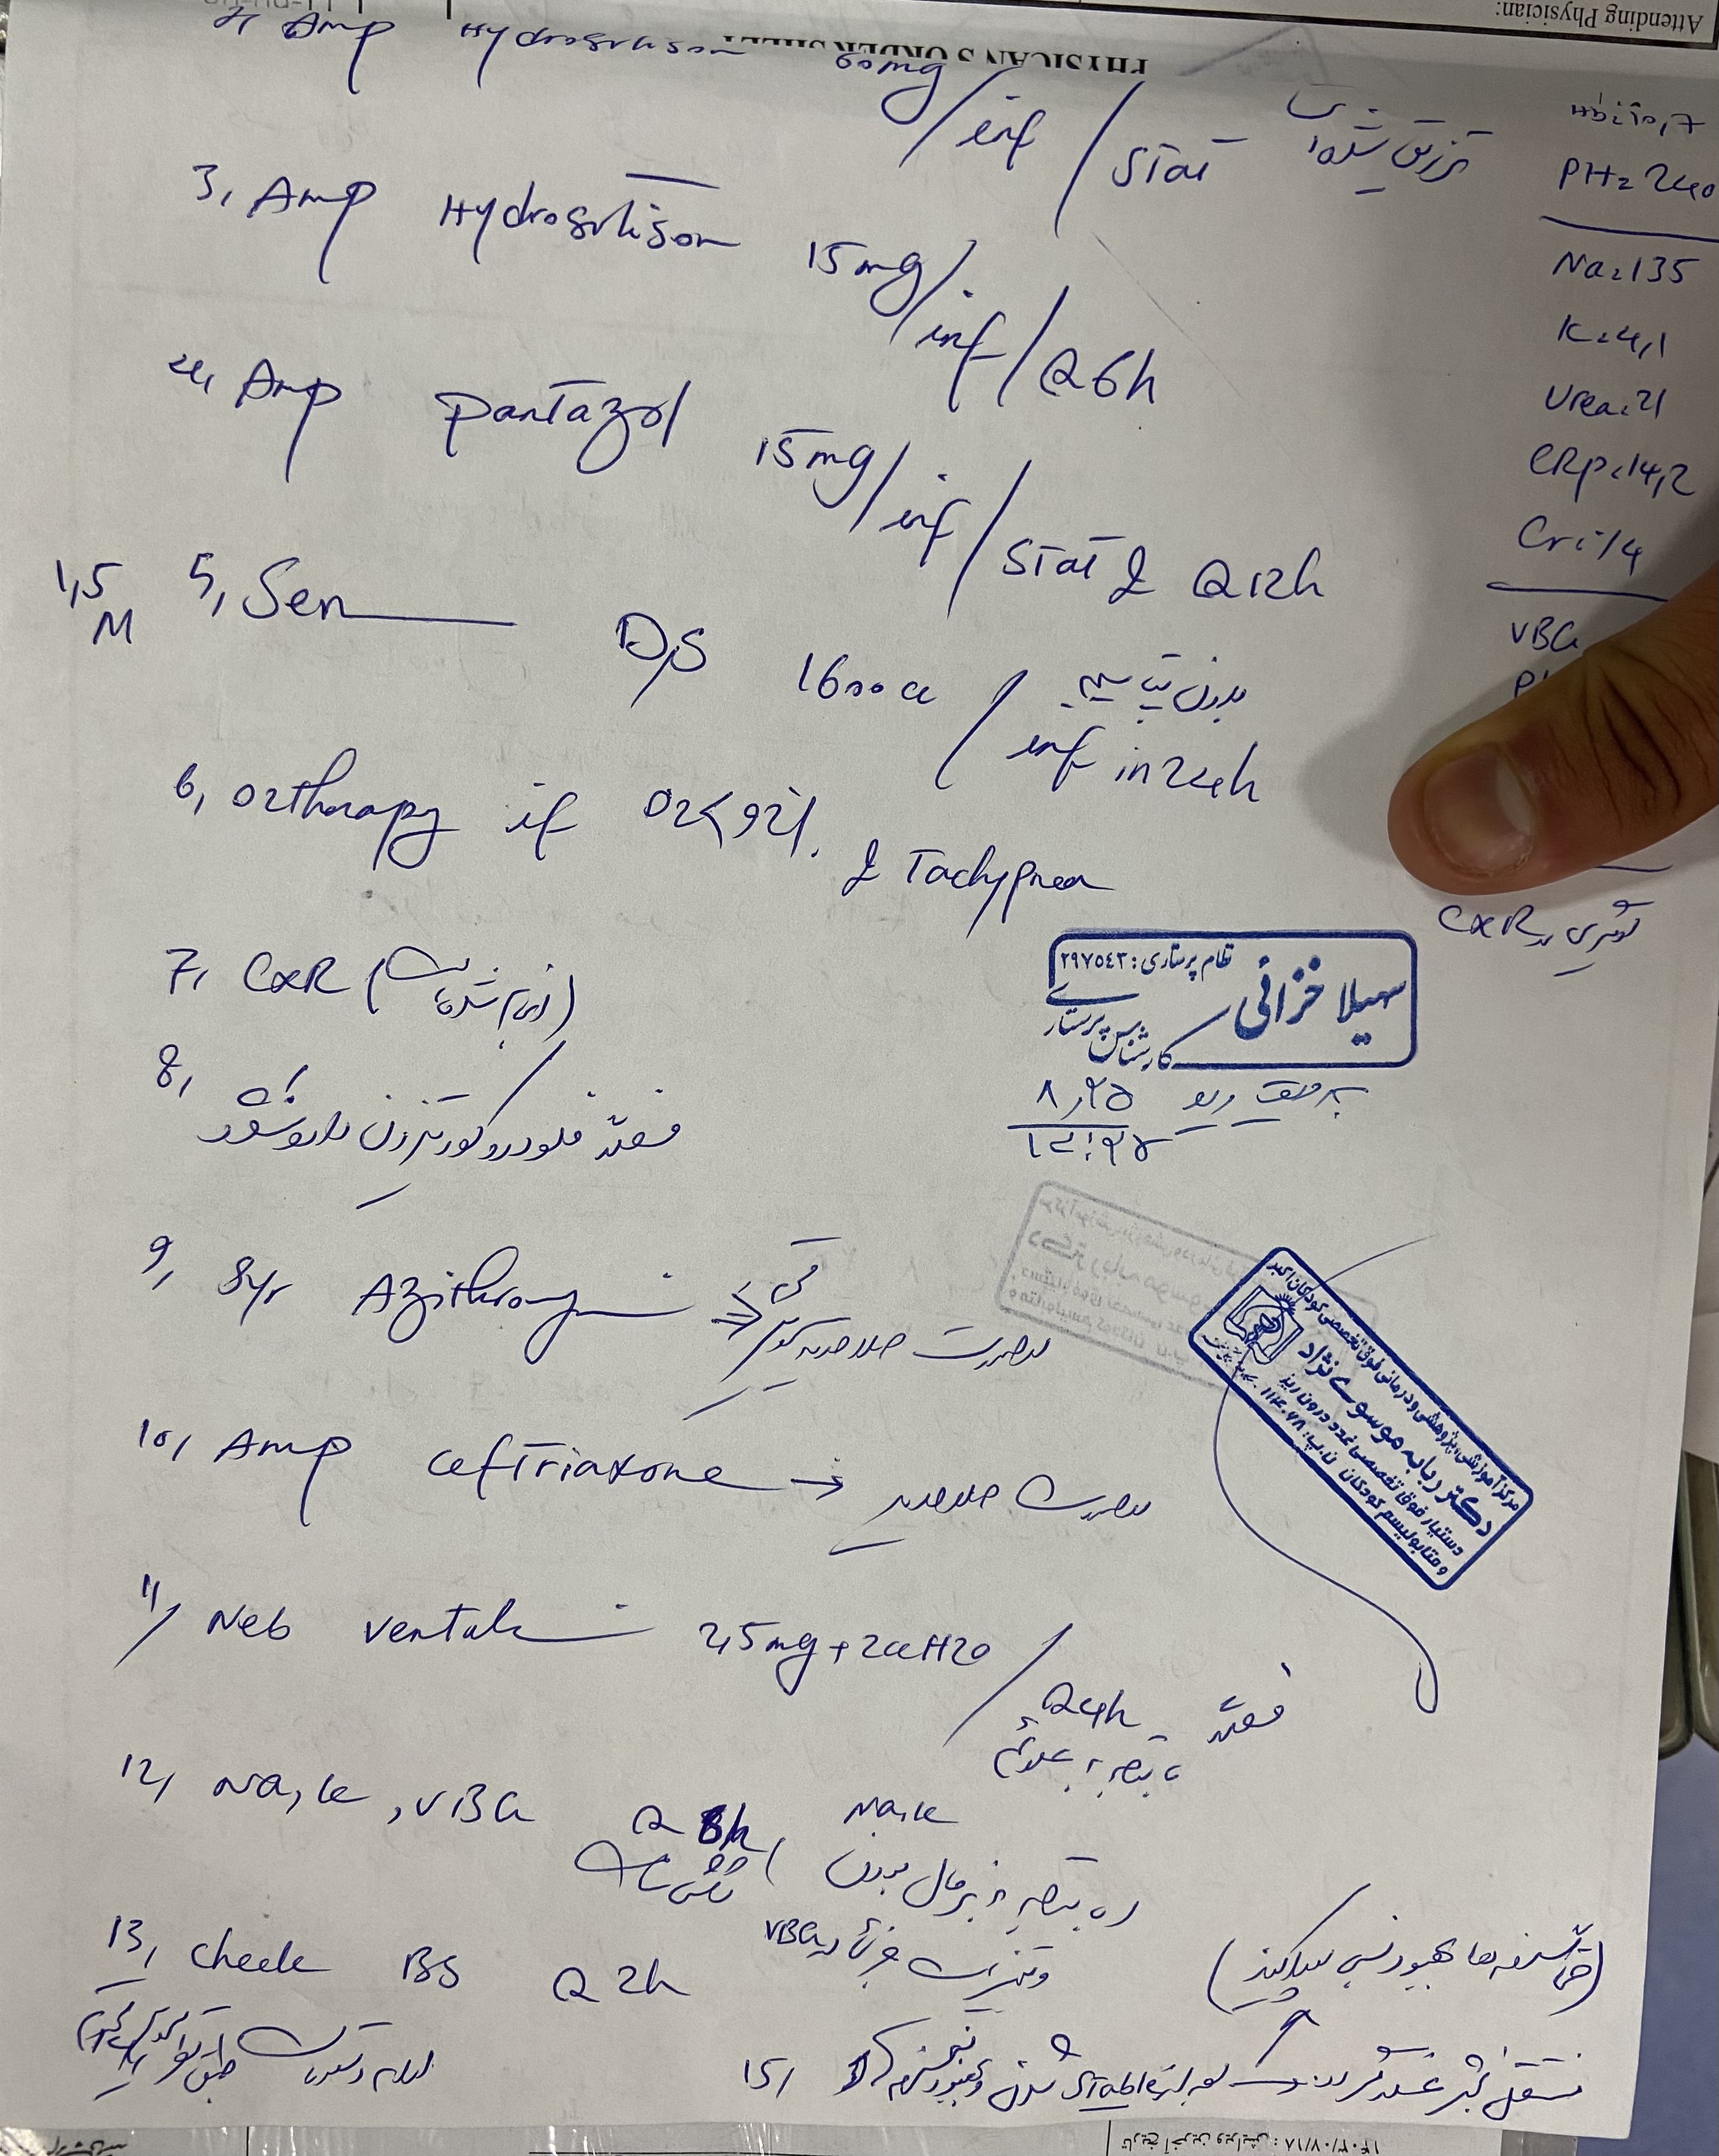

هیدروکورتیزون ۱۰ میلی

هر ۸ ساعت

فلودروکورتیزون هر ۸ ساعت / دوز دوبرابر شده بعد از بروز علایم

پسر 2ساله ونه ماه با تب وسرفه وابریزش و۳ بار استفراغ از دیشب به اورژانس مراجعه کرده مورد cah از ۱۷ روزگی تحت درمان با هیدروکورتیزون و فلودروکورتیزون بوده با شک به کریز ادرنال بستری شدن تاکی پنه وتاکی کاردی داشته

اقدامات